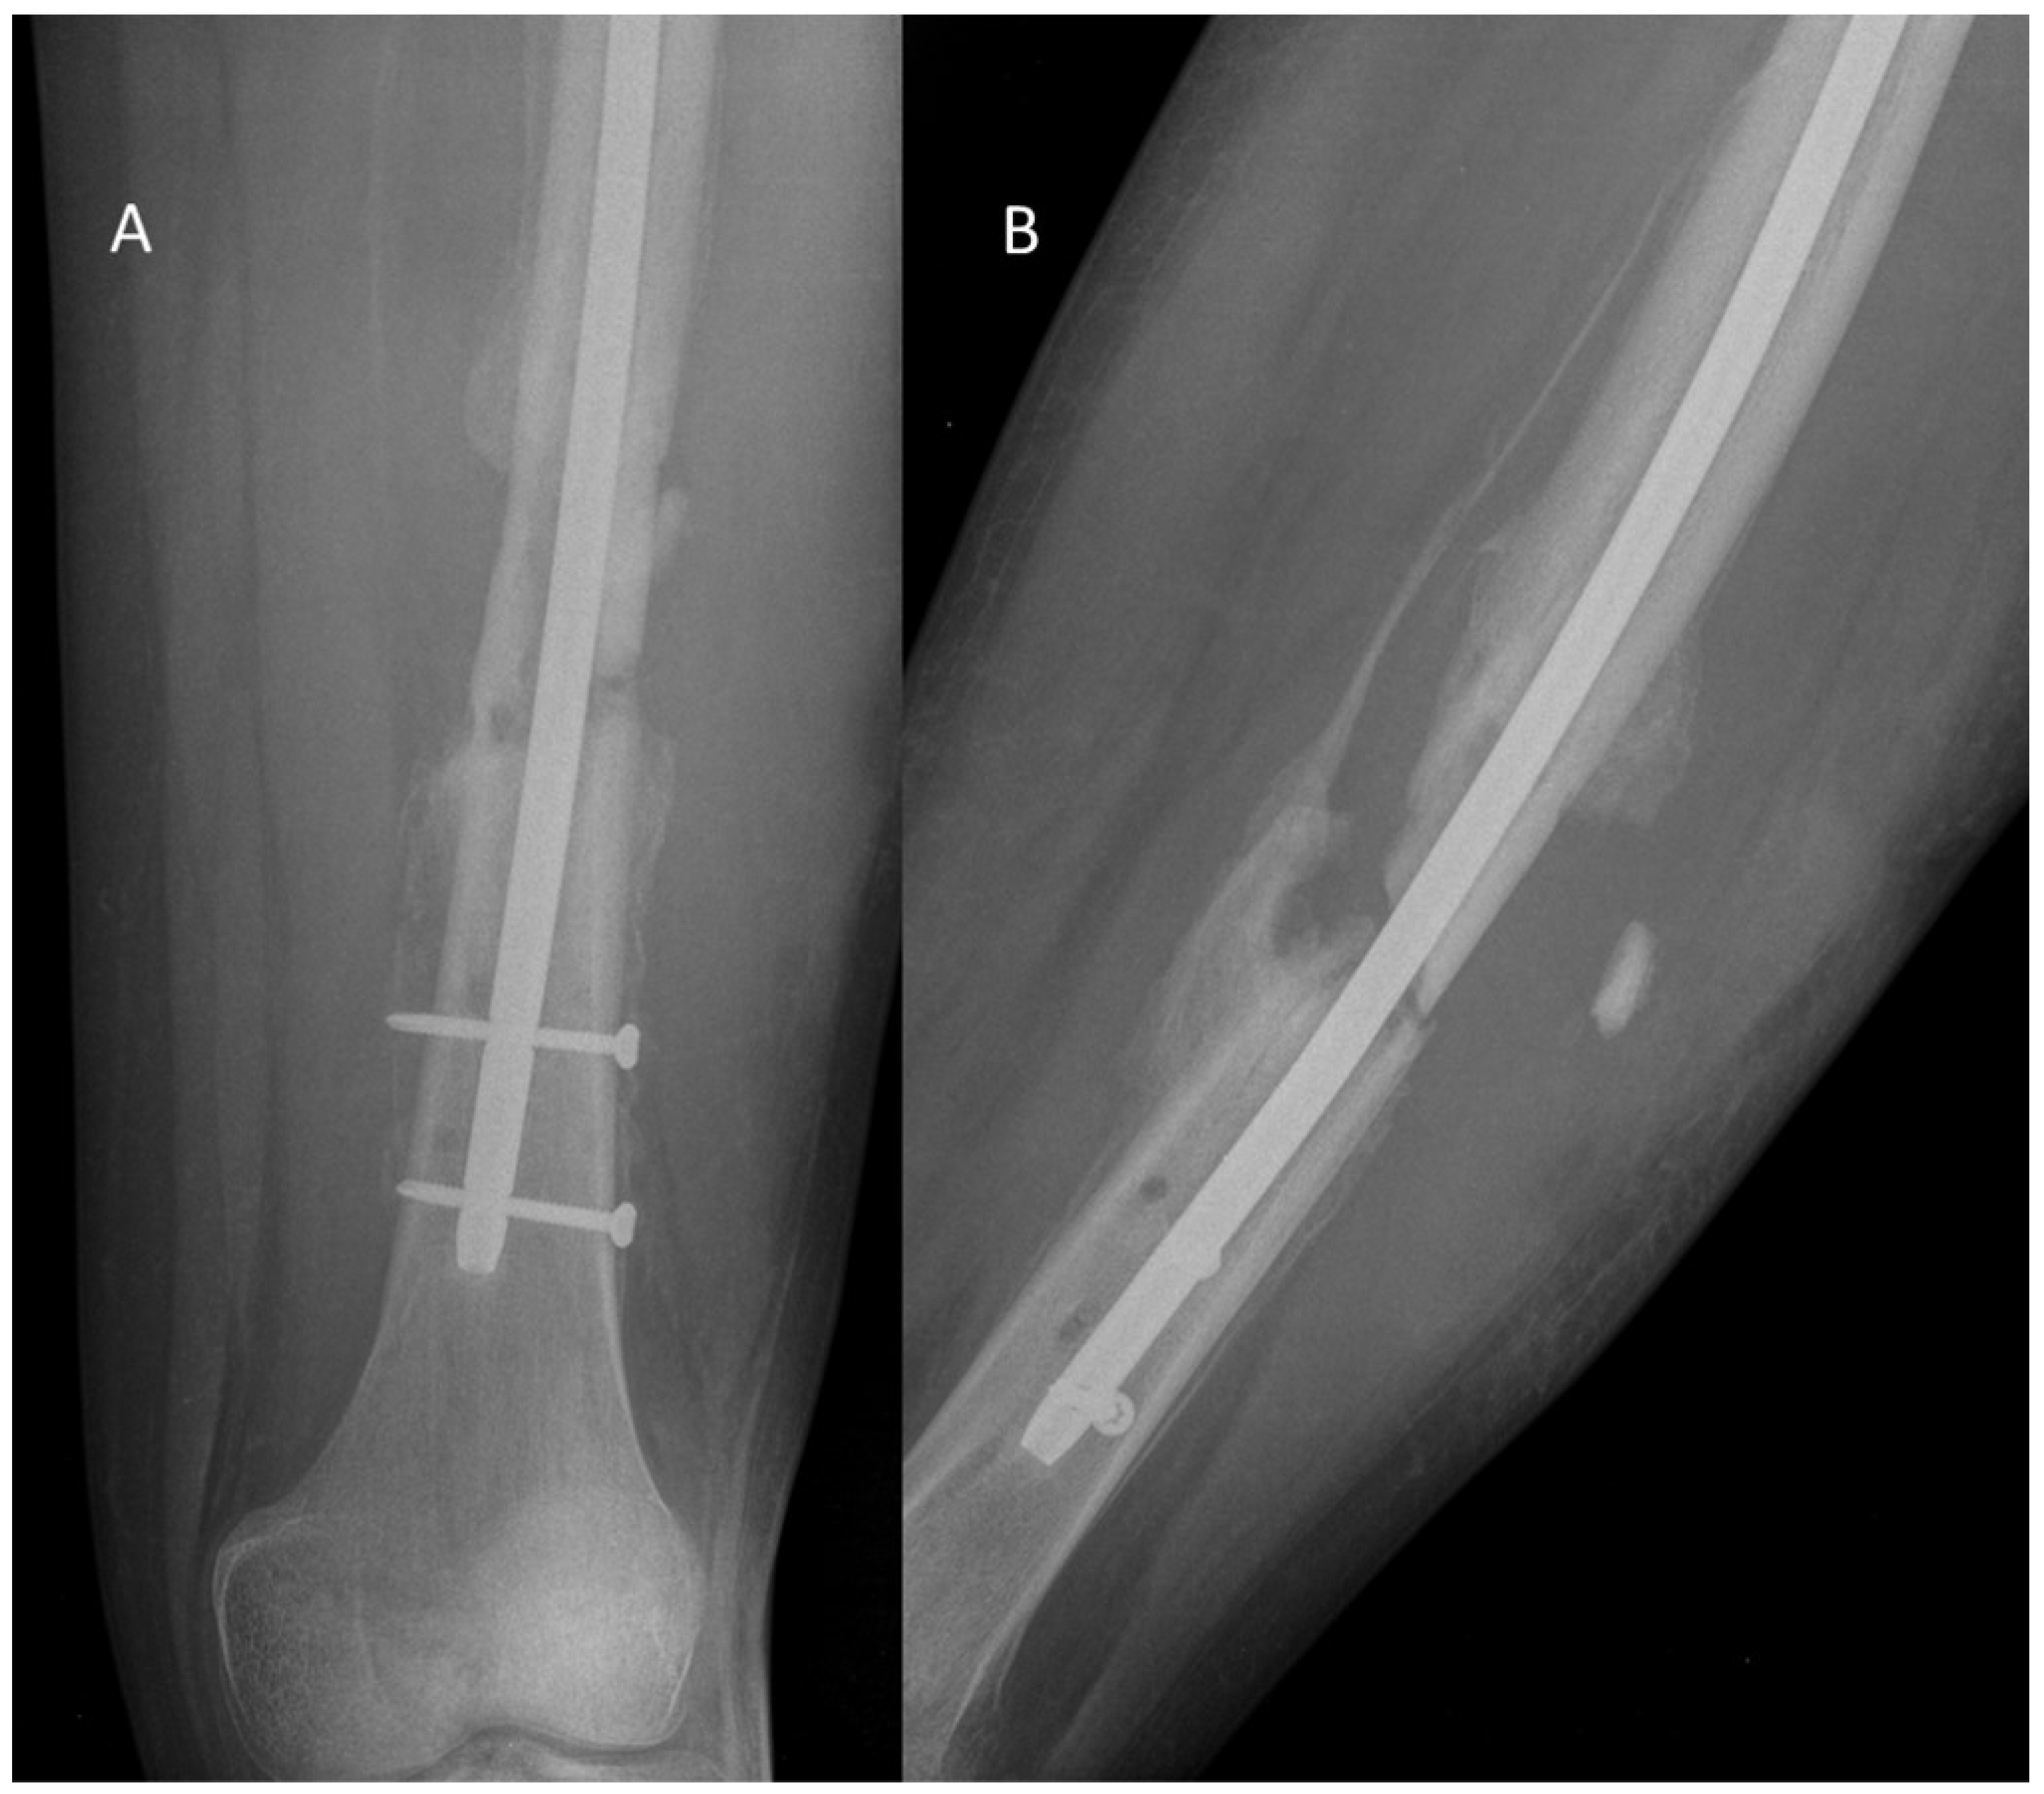

- Direct contamination occurs through open fractures, surgical procedures for fracture treatment, and puncture wounds. Most infected fractures arise following open fracture repair or surgical intervention for closed fractures. A metallic implant is commonly associated with these infections [2].